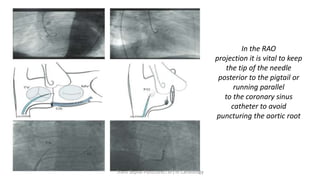

In the RAO

projection it is vital to keep

the tip of the needle

posterior to the pigtail or

running parallel

to the coronary sinus

catheter to avoid

puncturing the aortic root

Check in RAO

(check needle tip away from Aorta

and CS)